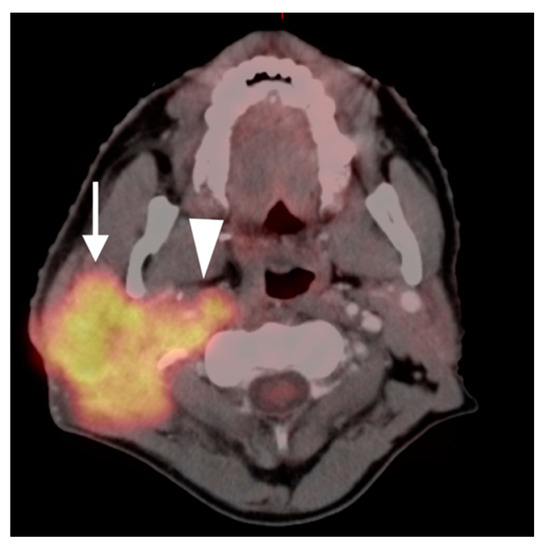

2.2. Squamous Cell Carcinoma of the Head and Neck (SCCHN)

- Oral cavity squamous cell carcinoma